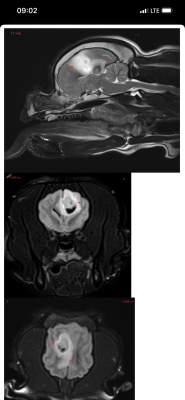

Вчера делали Марику МРТ в клинике Skolkovo Vet, если кому-то интересно, стоит чуть больше 12000₽. Результат неутешительный. Заключение:

МР-признаки новообразования в области лобной и теменной долей коры больших полушарий головного мозга справа, с очагами кровоизлияния и перифокальным отеком.

МР-признаки постсудорожных изменений.

Опухоль у моего мальчика(( она и вызывает судороги. Написала сегодня в вотс ап Хохлову, не знаю ответит ли, готова ехать к нему в клинику если он вообще принимает пациентов. К Дубовицкой попасть нереально, там очередь минимум на 1,5 месяца, есть онлайн консультация, стоит как и очный прием 7000₽, но ее рекомендуют скорее как второе мнение после очного осмотра у невролога. Рекомендовали еще Субботина из Белого Клыка, но увы, он по известным всем причинам с 2022 работает в вет клинике в Грузии. Продолжаю давать Кеппру и Габапентин

Итак, в прошлую субботу, когда въезд в Москву перегородили танки, над городом кружили вертолеты и не работала навигация, мы с Мариком были на приеме у уважаемого Алексея Валерьевича Хохлова. Он изучил снимки головного мозга, опухоль Марика он назвал скорее кистой и предположил, что живет он с ней уже давно, естественно ни о каком оперативном вмешательстве речи не идет. Спустя неделю после эпистатуса Марик почти полностью восстановился, но по лестнице сам еще не поднимается, Хохлов его состоянием доволен и никаких тревожных симптомов не обнаружил. Он прописал: Паглюферал1 - по 1/4 2 раза в день, Габапентин 300 по 1/2 2 раза в день, Кавинтон 5мг по 1/4 2 раза в день. Кеппру не прописал! Так же выдал рекомендации и список лекарств если будут приступы, что и как колоть, но эти схемы тут всем давно известны. Неделю мы принимаем все вышеизложенные препараты, пока все нормально, живем дальше с Божьей помощью!